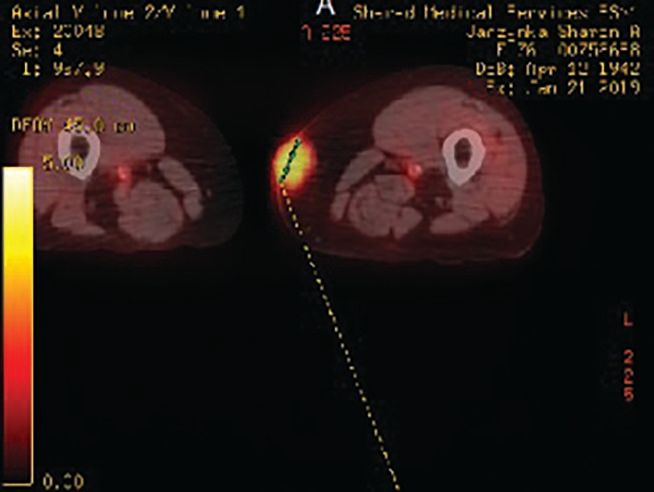

A woman, aged 76 years, presented with a bluish-purple lump in her mid- to upper medial left thigh. It started initially as a flat rash, and over a 2-month period, it turned into a mass measuring 2.5 cm by 3.1 cm (Figure 1). Work-up, including a PET-CT scan, showed the soft tissue mass on the inner thigh to have a Standardized Uptake Value of 4 (Figure 2); there were no other sites of disease. A biopsy of the lesion was performed (Figure 3).